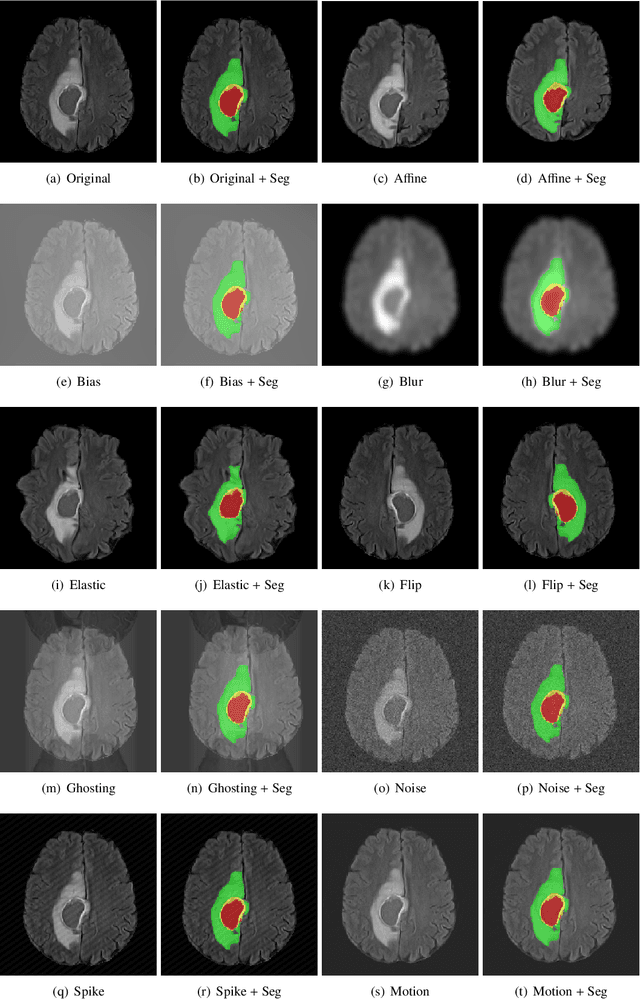

Abstract:Deep Learning (DL) has greatly highlighted the potential impact of optimized machine learning in both the scientific and clinical communities. The advent of open-source DL libraries from major industrial entities, such as TensorFlow (Google), PyTorch (Facebook), and MXNet (Apache), further contributes to DL promises on the democratization of computational analytics. However, increased technical and specialized background is required to develop DL algorithms, and the variability of implementation details hinders their reproducibility. Towards lowering the barrier and making the mechanism of DL development, training, and inference more stable, reproducible, and scalable, without requiring an extensive technical background, this manuscript proposes the \textbf{G}ener\textbf{a}lly \textbf{N}uanced \textbf{D}eep \textbf{L}earning \textbf{F}ramework (GaNDLF). With built-in support for $k$-fold cross-validation, data augmentation, multiple modalities and output classes, and multi-GPU training, as well as the ability to work with both radiographic and histologic imaging, GaNDLF aims to provide an end-to-end solution for all DL-related tasks, to tackle problems in medical imaging and provide a robust application framework for deployment in clinical workflows.